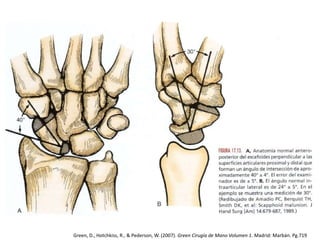

ANATOMÍA

• Recubierto de cartílago

• 5 Superficies articulares

– Radio

– Semilunar

– Hueso grande

– Trapecio

– Trapezoide

• Superficie distal palmar

respecto a la proximal

• Inserciones ligamentosas

– L. interóseo escafolunar

– L. radioescafogrande

– L. trapecioescafoideo

– L. escafogrande